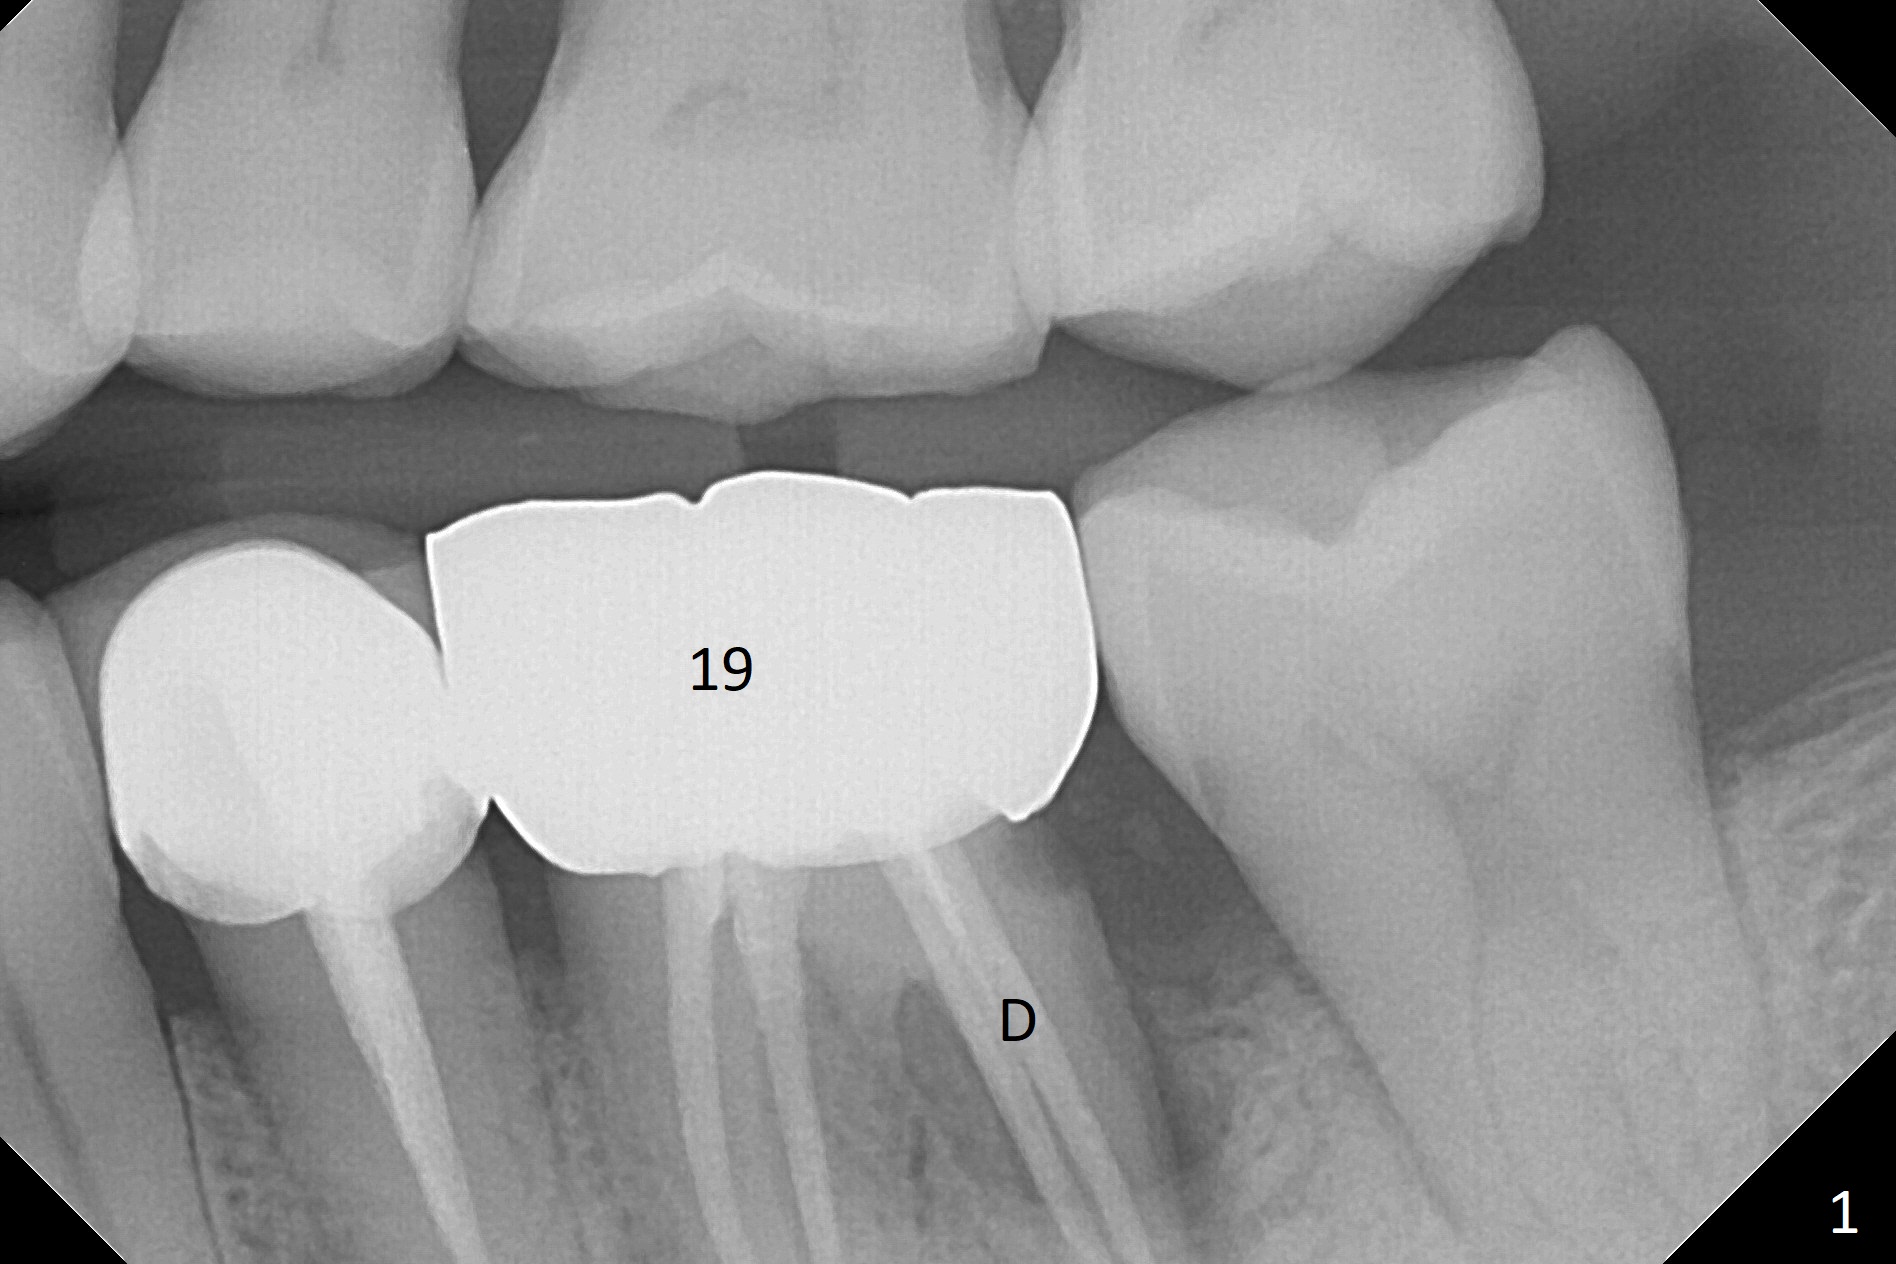

A 54-year-old man has distal (D) root fracture at #19 while the implant at #2 is osteointegrarting (Fig.1,2). Because of the large distal defect (Fig.3, after extraction), osteotomy (red line) will be initiated in the mesial socket (Fig.4, as distal as possible, with the coronal end in the middle of the socket) or the mesial slope of the septum (Fig.5) so that the implant (green) will be supported by the distally displaced septum (Fig.6 arrow). CT taken 8 months later confirms distal root fracture. A 6x11.5 mm or longer implant seems to be appropriate for the site (Fig.7). Three years later there is severe buccal swelling (Fig.8) with vertical mesial and distal root fractures (Fig.9). Although the buccal plate is lost, the septum remains (Fig.10 S), which will provide with blood supply to the bone graft (Fig.11), covered with Bioxclude and 6-month membrane and PSA suture. The bone density in the mesial and distal sockets is higher than that in the septum 8 months post cortical bone graft (Fig.12). In spite of bone graft, the buccolingual width reduces by almost 4 mm 8 months post extraction (Fig.3,4). In spite of bone graft, the buccolingual width reduces by almost 4 mm in 8 months post extraction (Fig.3,4). A 5x11.5 mm implant will be placed (Fig.15).